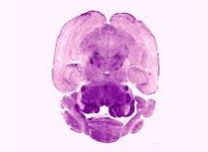

• Attain a knowledge and understanding of basic neuroanatomy